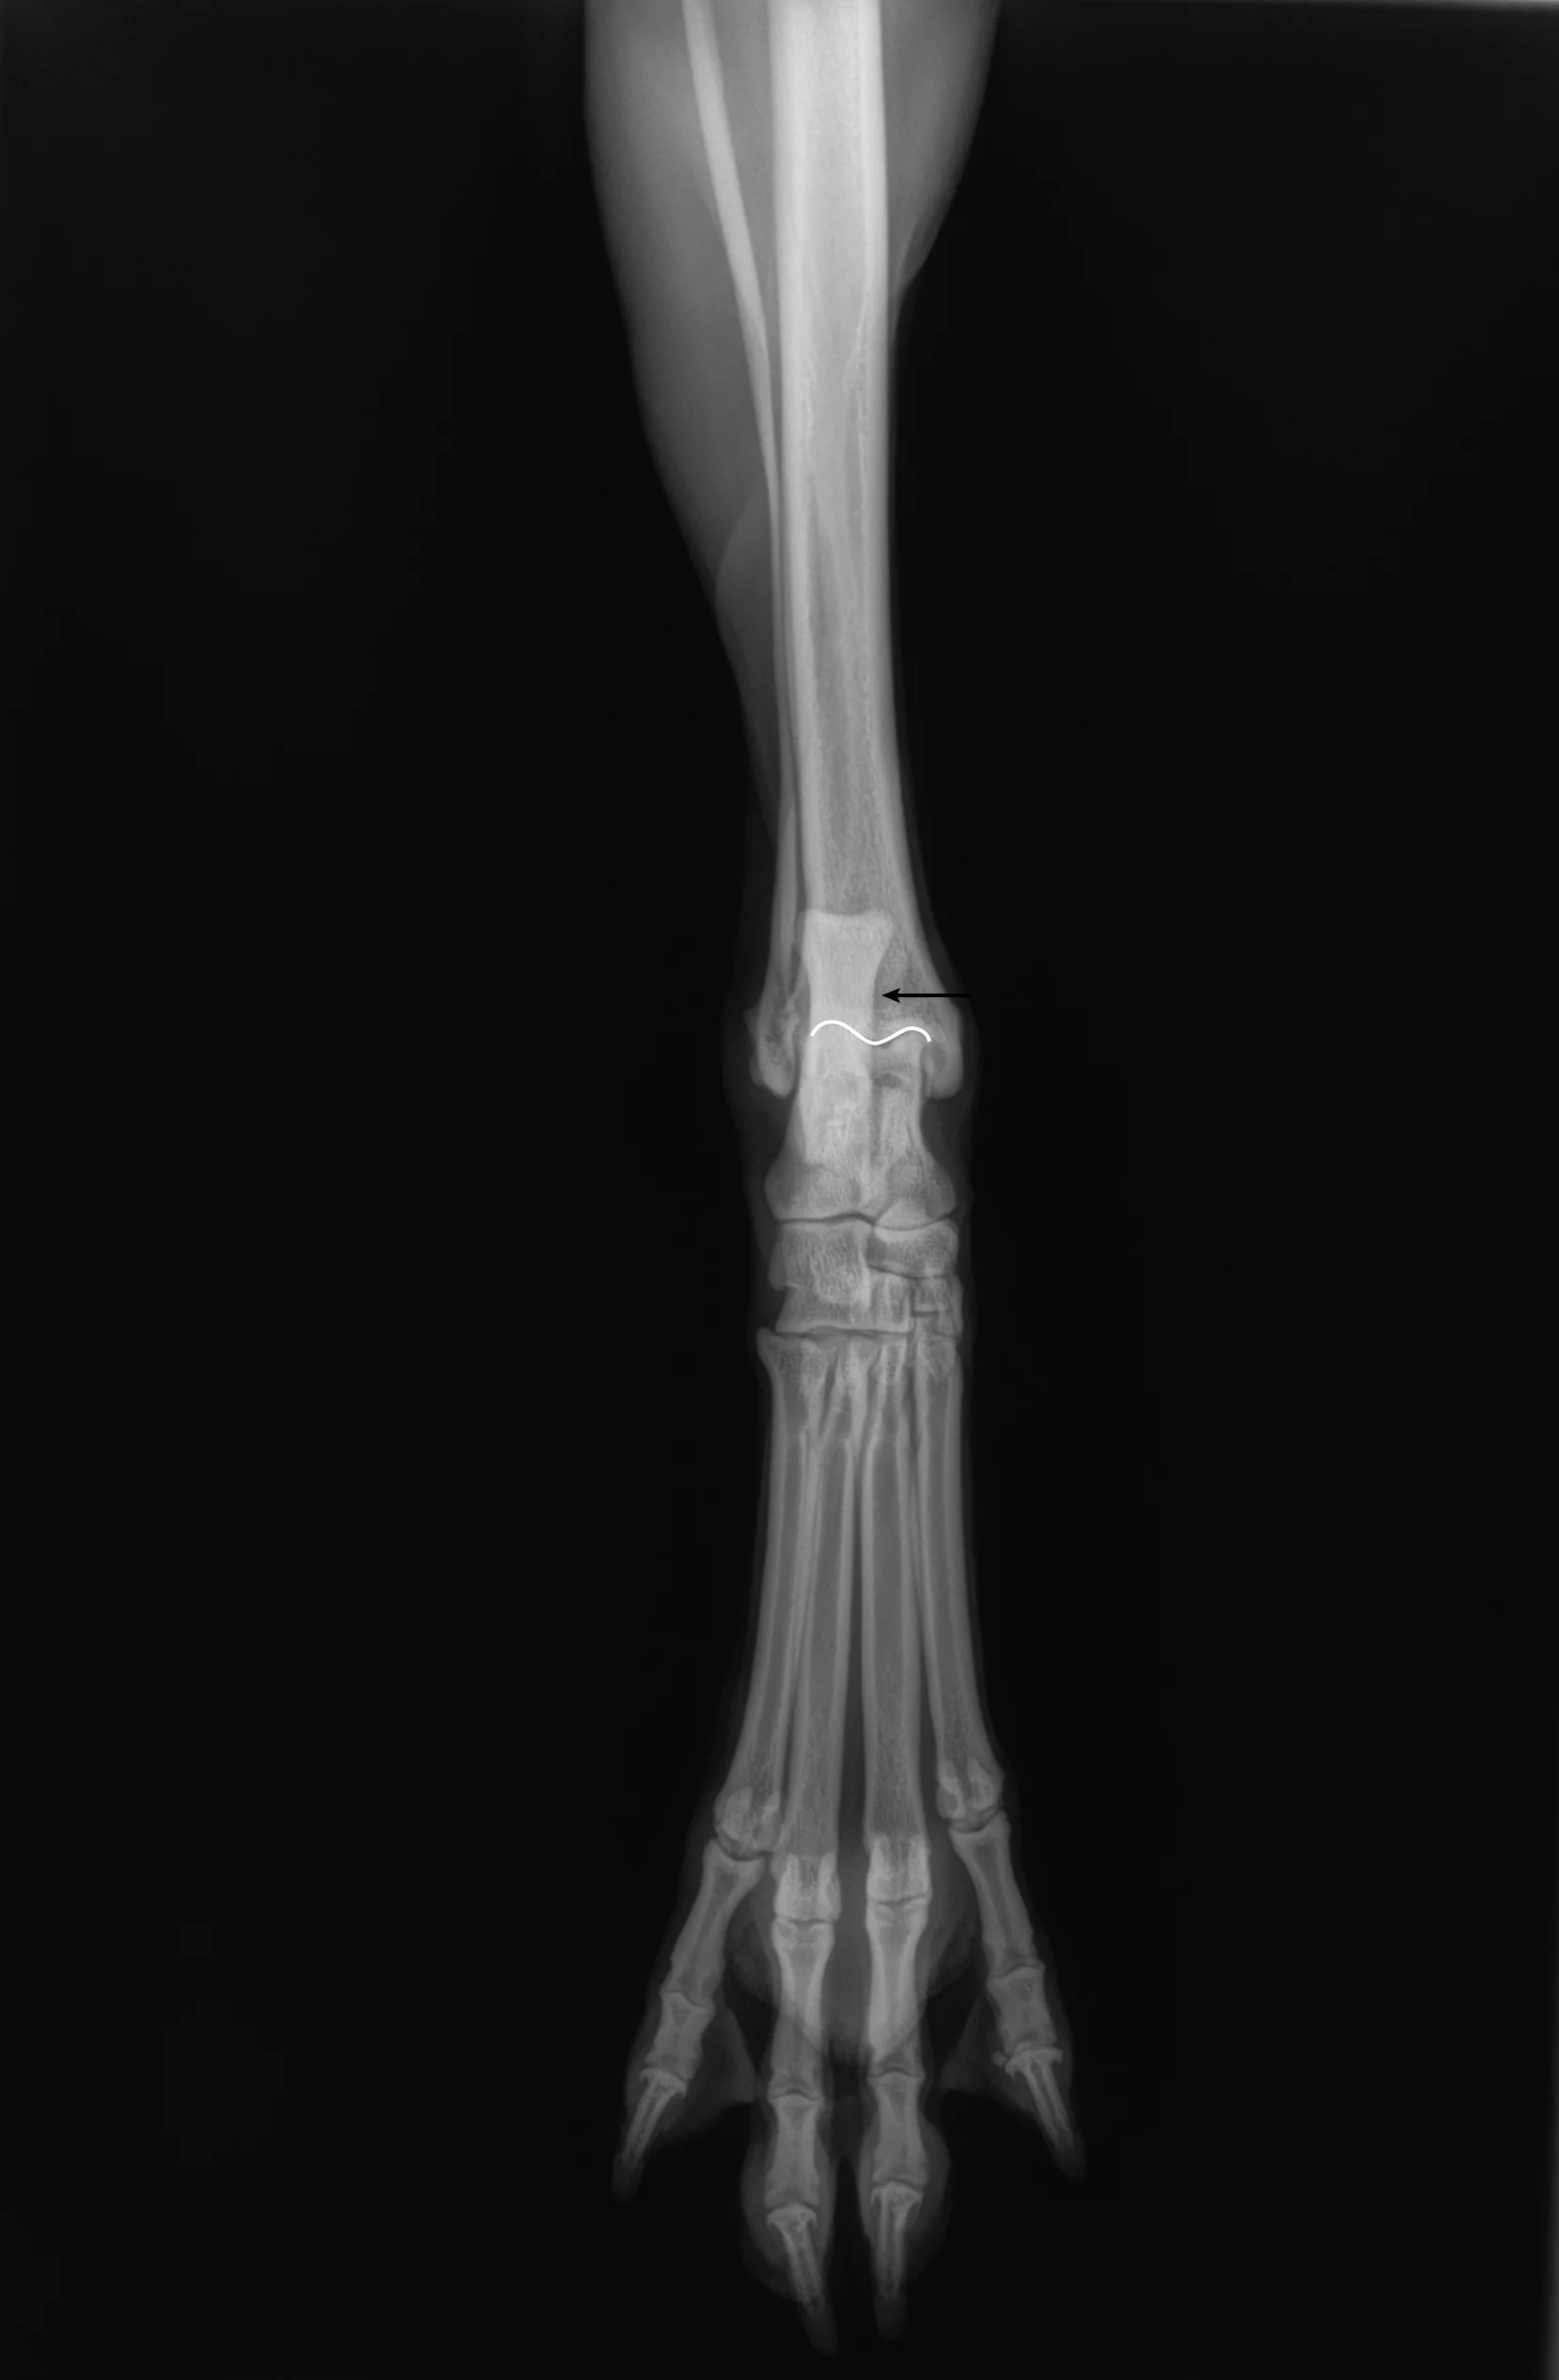

Author Insight

On the radiograph, the stifle and tarsus should be at an »90-degree angle. The patella should be cranial (white arrow), and the medial and lateral femoral condyles should be as superimposed as possible. The medial and lateral fabellae should have near superimposition to each other (black arrow).